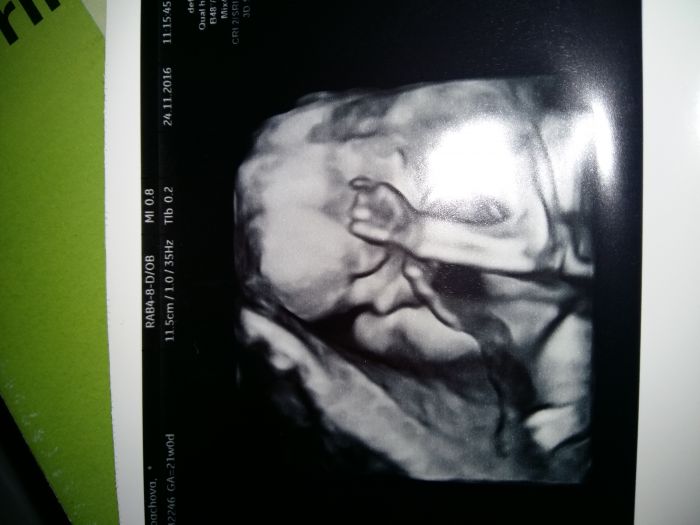

, ale sleduji vas bedlivě... Přeji všem hlavně zdravíčko a zdravá miminka... Zkusím dát fotecku malýho Lukáška

[957596] Jee to jsou krásný fotečky :)) Mně na screeningu 3D nedělala, ani mi to nenabídla. Tak jsem se na to včera ptala v poradně, a jsem objednaná na 23.12., tak snad nám Adámek ukáže před Vánoci tvářičku a budeme mít hezkej dáreček. Včera v poradně jsem se musela smát...při UTZ byl malej krásně otočenej k nám, bylo vidět jak otvírá pusinku a jakoby mlaskal. Měla jsem zrovna v puse bonbon, třeba to cítil

a tady ještě fotečka našeho prcka :))